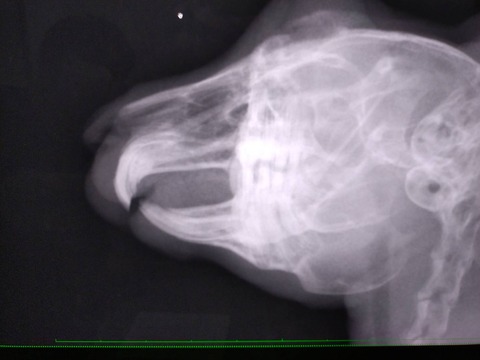

9/7 去勢手術 口腔内検査も一緒に行いました。

臼歯左上手前から2番目、左下1.2.4番目 外側に少し尖っている歯があり、念の為カットしました。